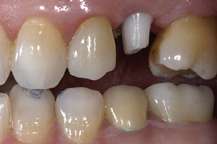

These are usually called prosthetic implant abutments. These abutments can be made from a variety of materials, such as titanium, surgical stainless steel and gold. More modern abutments are now also made from zirconia,[3] which is a white ceramic, to better complement the aesthetics of a dental implant restoration. The two images to the right show a ceramic abutment and the ceramic crown bonded to it. The images to the right show how a ceramic abutment can enhance a ceramic crown by giving it a more lifelike appearance. Ceramic abutments have to be used with care, however, since their compressive strength is nowhere near that of titanium, gold or other noble metals. Most clinicians feel more comfortable using a metal prosthetic abutment in the posterior molar areas, due to the increased masticatory forces present in these areas.